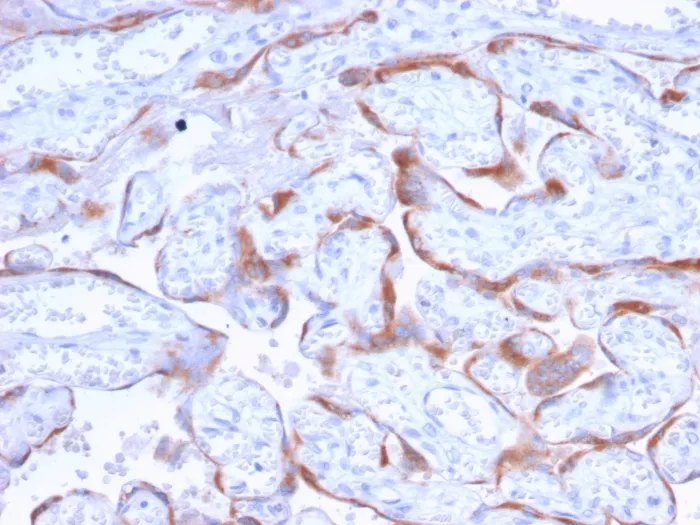

IHC, FFPE (verified)Validated Applications:

IHC, FFPEPositive Control: